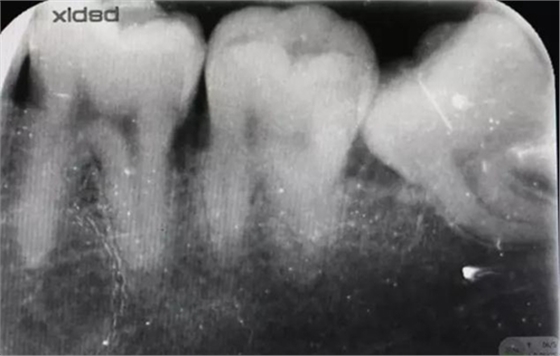

圖1.術(shù)前x線根尖片影像:38牙冠近中傾斜,雙根、近中根遠中彎曲